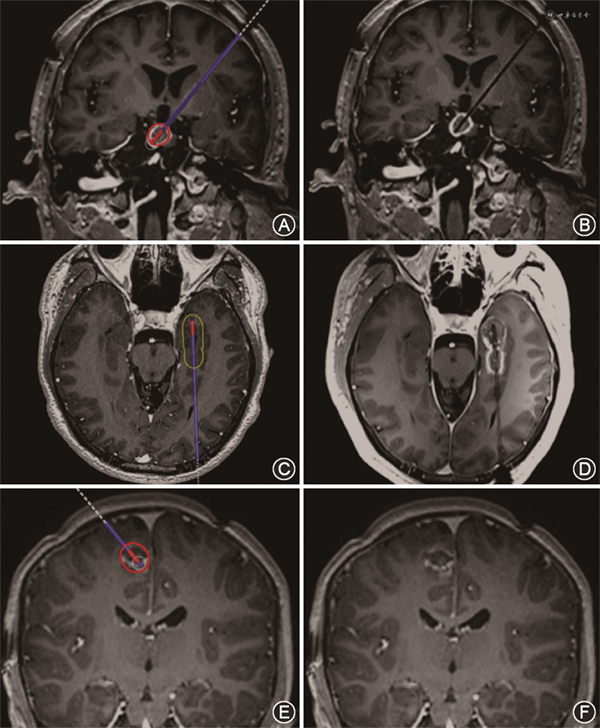

3.手术过程:治疗过程共分为两部分:机器人引导激光光纤套管置入和MRgLITT(图1)。(1)机器人引导激光光纤套管置入:患者局部麻醉置入颅骨Marker并进行CT薄扫后与磁共振图像配准,进行机器人导航注册。手术采取全身麻醉,使用磁共振兼容头架固定头部并连接手术床和立体定向机器人,导入手术计划后注册,消毒铺巾后钻孔、刺破硬脑膜并使用探针保证光纤套管通路顺畅。安装导向螺钉,最后按深度置入冷却套管并置入光纤并进行核磁扫描确定光纤位置后准备进行LITT。(2)MRgLITT:将冷却套管妥善连接,将磁共振基准序列配准,确定光纤位置满意后,将光纤轴向MRI作为基础勾画间质热疗区域和温度监控区域,在序列上勾画多个矩形区域作为温度计算中的参考区域。设定光纤发射模式,启动循环冷却水,确定光纤发射参数并启动,同时进行MRI实时温度监控,设定区域超过警戒温度会发出警报并停止。必要时可以回退光纤进行重复间质热疗,在全部间质热疗结束后,扫描增强核磁确定间质热疗范围。确认满意后移出激光光纤套管,缝合包扎。

共纳入接受MRgLITT患者22例,男12例,女10例,年龄3~45岁(24±13岁)。包括局灶皮质发育不良(FCD)7例,MTLE 5例,HH 3例,低级别胶质瘤3例,灰质异位1例,结节性硬化1例,海绵状血管瘤1例,多灶性癫痫1例。22例患者共进行24靶点毁损,其中21例患者行致痫灶毁损,1例多灶起始患者行胼胝体离断。手术时间101~308(173±49)min,手术出血1~5(3.7±1.6)ml,手术后3~10(5.5±1.8)d出院。体积间质热疗比为87.3%~97.0%,平均92.6%。其中1例累及中央区患者进行了术中唤醒磁共振引导激光间质热疗,其余均为全身麻醉下操作。不同癫痫类型患者术后即刻增强磁共振显示的毁损范围与计划的毁损范围相比基本相同(图2)。